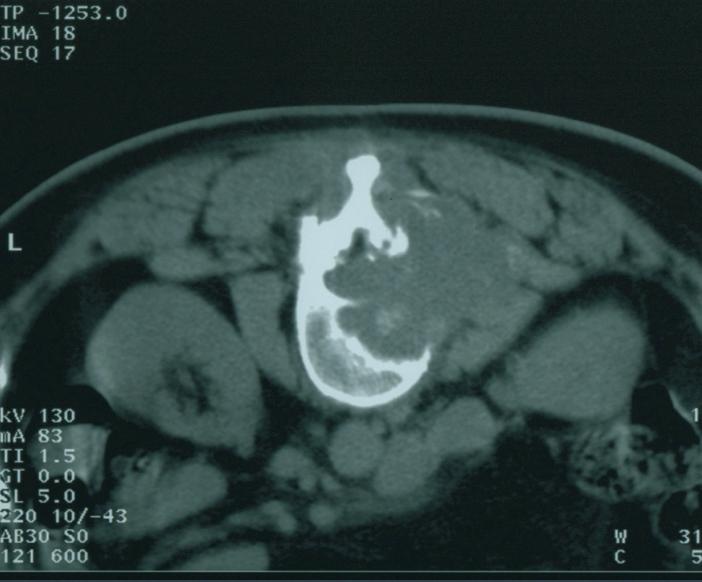

碘125粒子源植入治疗原发性肝癌

碘125粒子源植入治疗椎旁软组织转移癌

术前

术后3个月病灶明显缩小